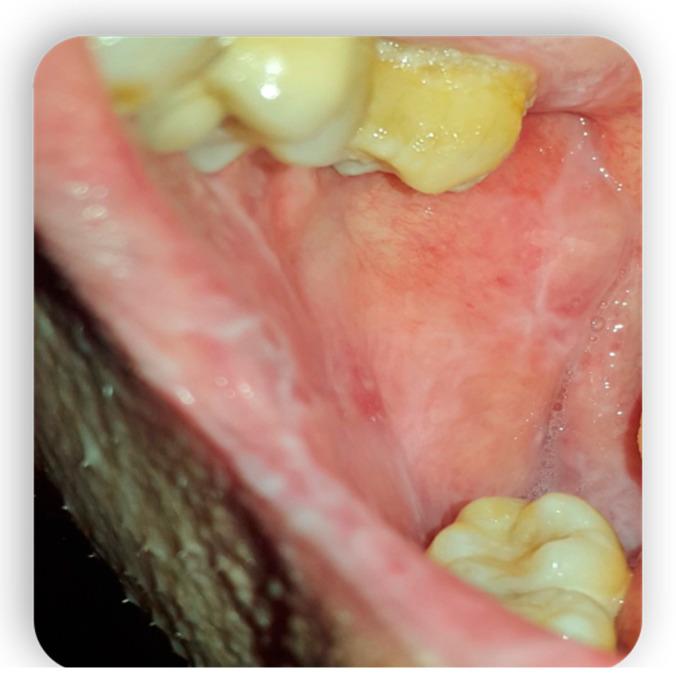

Graft-versus-host disease (GVHD) is a complication of hematopoietic stem cell transplantation (HSCT). GVHD may also develop following solid transplants or blood transfusions if white blood cells are transferred. GVHD affects multiple organs, including the oral tissues. This pictorial review provides a background of GVHD to dental practitioners, describes the most common oral manifestations of GVHD, and highlights the main treatment modifications needed to deliver dental care to patients with GVHD. A narrative review enriched with clinical data was performed by searching the scientific literature for all articles regarding GVHD and oral manifestations/therapies. All articles without exclusion criteria, except animal tests, were included in the above review. Acute GVHD may manifest in the oral mucosa; however, it often develops immediately following HSCT when routine dental treatment is postponed. Chronic GVHD may manifest in the oral mucosa, the salivary glands, and the musculoskeletal compartment. It may indirectly affect the teeth and the oral flora, putting the patient at risk for infections. Importantly, GVHD poses an increased risk for oral cancer. GVHD has a wide range of oral manifestations, some of which may affect dental treatment.